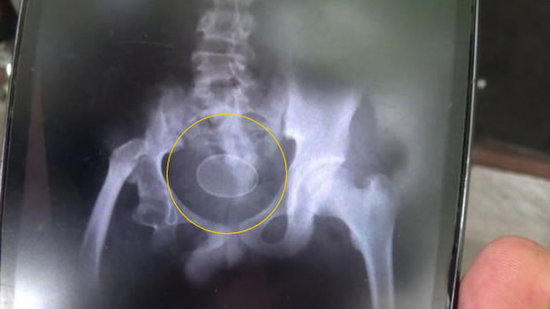

只因父亲责备玩手机 11岁男孩一时冲动切下左